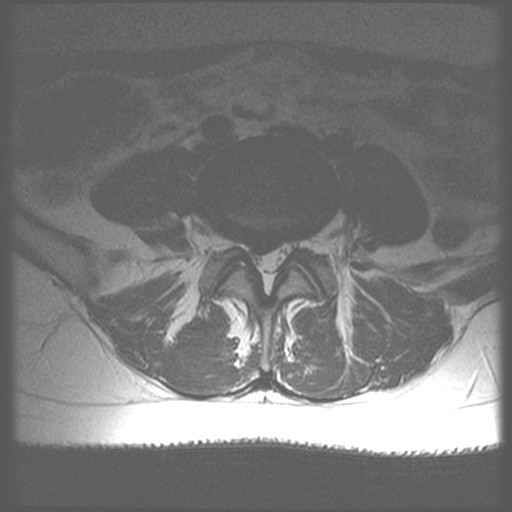

LWZ